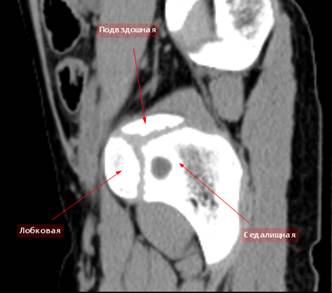

РК

– томография таза ребенка 10 лет, саггитальный скан через дно вертлужной

впадины. Отчетливо виден хрящ, соединяющий три тазовые кости. Он имеет форму

буквы Y.